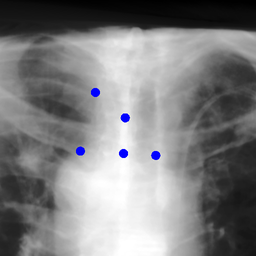

Shift-Invariant Tracking. The POINT network benefits from the shift invariant property of the convolution operation, which makes it less sensitive to the in-plane offset of the DRRs. Figure 8 shows some tracking results from the POINT network. Here the odd rows show the (a) X-ray and (b-d) DRR images. The heatmap below each DRR shows the tracking result between this DRR and the leftmost X-ray image. The red and the blue marks on the X-ray and DRR images denote the POIs. The red and the blue marks on the heatmaps are the ground truth POIs and the tracked POIs, respectively. The green blobs are the heatmap responses and they are used to generate the tracked POIs (blue) according to Equation (7). The numbers under each DRR denote the mPD scores before and after the tracking. As we can observe that the tracking results are consistently good, no matter how much initial offset there is between the DRR and the X-ray image. This shows that our POINT network indeed benefits from the POI convolution layer and provide more consistent outputs regardless of the in-plane offsets.

Refer to caption

(a)

(b) 13.6 \rightarrow 7.3

(c) 22.9 \rightarrow 9.0

(d) 37.1 \rightarrow 7.8

(e)

(f) 19.5 \rightarrow 8.7

(g) 26.0 \rightarrow 9.5

(h) 41.1 \rightarrow 11.4

(b)

(c)

(d)

Figure 8: POI tracking results. (a) X-ray image. (b-d) DRR images with different in-plane offsets. The heatmaps of the tracking results are all aligned with the X-ray images and appear similar, showing the shift-invariant property.